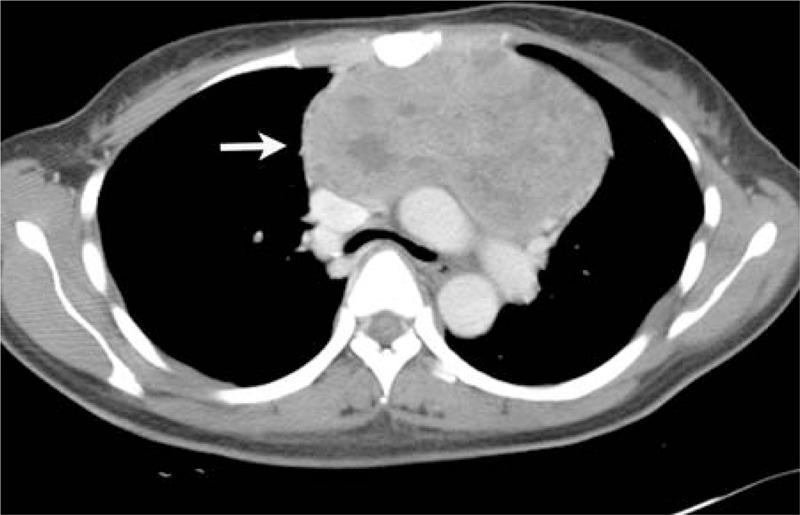

The aim of the study was to describe the imaging findings of Askin tumors on computed tomography (CT) and fluorine 18 fluorodeoxyglucose-positron emission tomography (FDG-PET/CT).Seventeen cases of Askin tumors confirmed by histopathology were retrospectively analyzed in terms of CT (17 cases) and FDG-PET/CT data (6 cases).Fifteen of the tumors were located in the chest wall and the other 2 were in the anterior middle mediastinum. Of the 15 chest wall cases, 13 demonstrated irregular, heterogeneous soft tissue masses with cystic degeneration and necrosis, and 2 demonstrated homogeneous soft tissue masses on unenhanced CT scans. Two mediastinal tumors demonstrated the irregular, heterogeneous soft tissue masses. Calcifications were found in 2 tumors. The tumors demonstrated heterogeneously enhancement in 16 cases and homogeneous enhancement in 1 case on contrast-enhanced scans. FDG-PET/CT images revealed increased metabolic activity in all 6 cases undergone FDG-PET/CT scan, and the lesion SUVmax ranged from 4.0 to 18.6. At initial diagnosis, CT and FDG-PET/CT scans revealed rib destruction in 9 cases, pleural effusion in 9 cases, and lung metastasis in 1 case. At follow-up, 12 cases showed recurrence and/or metastases, 4 cases showed improvement or remained stable, and 1 was lost to follow-up.In summary, CT and FDG-PET/CT images of Askin tumors showed heterogeneous soft tissue masses in the chest wall and the mediastinum, accompanied by rib destruction, pleural effusion, and increased FDG uptake. CT and FDG-PET/CT imaging play important roles in the diagnosis and follow-up of patients with Askin tumors.

本研究的目的是描述Askin肿瘤在计算机断层扫描(CT)和氟-18氟脱氧葡萄糖正电子发射断层扫描(FDG-PET/CT)上的影像学表现。对17例经组织病理学确诊的Askin肿瘤病例进行回顾性分析,分析其CT(17例)和FDG-PET/CT数据(6例)。15例肿瘤位于胸壁,另外2例位于前纵隔中部。在15例胸壁病例中,13例表现为不规则、不均匀的软组织肿块,伴有囊性变和坏死,2例在平扫CT上表现为均匀的软组织肿块。2例纵隔肿瘤表现为不规则、不均匀的软组织肿块。2例肿瘤发现有钙化。增强扫描时,16例肿瘤表现为不均匀强化,1例表现为均匀强化。FDG-PET/CT图像显示,所有6例行FDG-PET/CT扫描的病例代谢活性均增加,病变SUVmax范围为4.0至18.6。初诊时,CT和FDG-PET/CT扫描显示9例有肋骨破坏,9例有胸腔积液,1例有肺转移。随访时,12例出现复发和/或转移,4例病情改善或保持稳定,1例失访。总之,Askin肿瘤的CT和FDG-PET/CT图像显示胸壁和纵隔有不均匀的软组织肿块,伴有肋骨破坏、胸腔积液和FDG摄取增加。CT和FDG-PET/CT成像在Askin肿瘤患者的诊断和随访中发挥着重要作用。